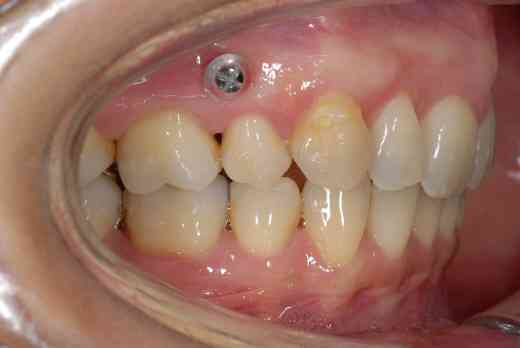

3 mois de mini vis et d'élastocs de classe II :-))

ça y est, on m'a enlevé les vis,...

n'empêche que 600 roros de vis de merde pour 3 mois, c'est un bon business moi je dis! pffffffffff

La question qu’on peut se poser est : pourquoi les vis ont-elles été placées un endroit où elles ne pouvaient que gêner le recul latéral supérieur qui avait justifié leur pose.

C’est dans doute pour cela qu’elles ont été enlevées au bout de trois mois seulement..